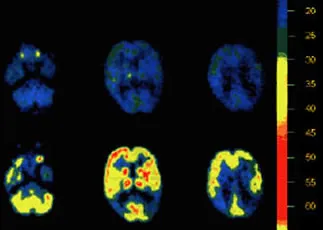

PET scans reveal brain chemistry in living individuals. This scan shows brain metabolism by blue (least glucose uptake) through yellow and red (maximum glucose uptake, indicating greater metabolic activity).

The top row of images shows the brain of a 59 year old woman at three different levels of her head. After the first scans were taken, she took 500 milligrams of PS a day for three weeks; the repeat scan at the bottom shows markedly improved brain activity. While the benefit waned at the end of this particular patient's six-month trial period, this image does graphically show what PS can do.[3]